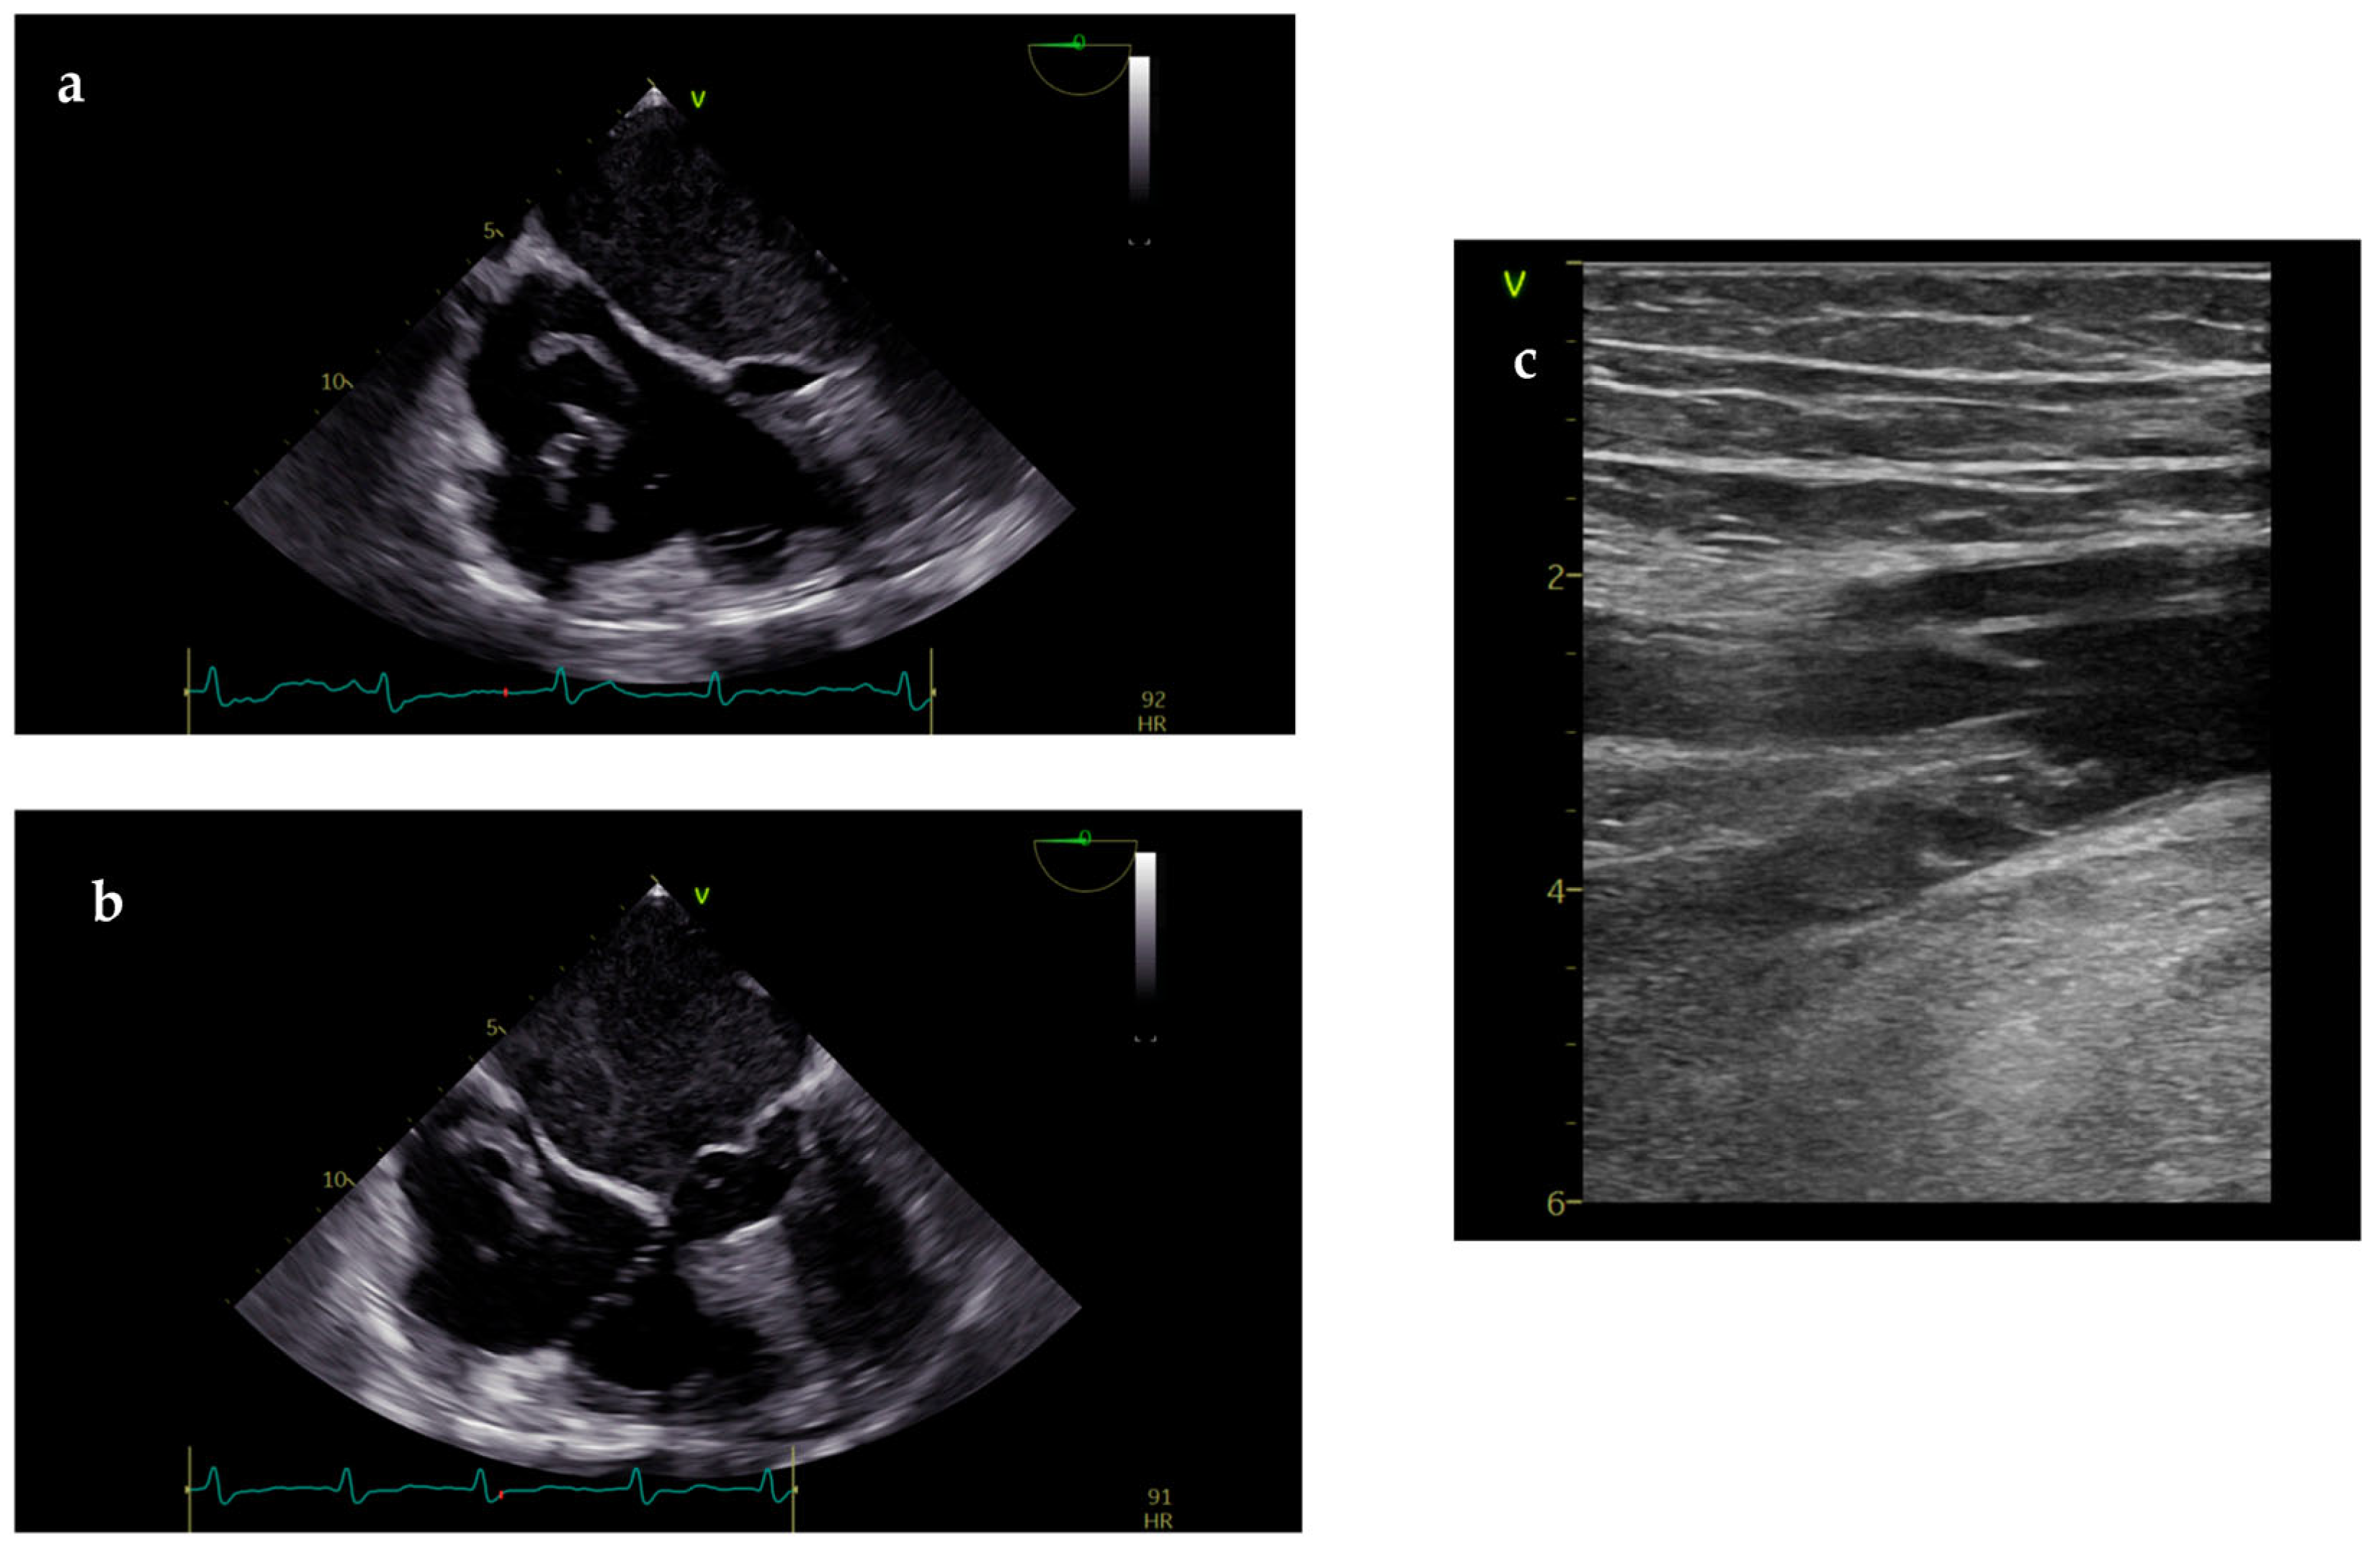

2.3. Role of Transesophageal Echocardiography

- Teran, F.; Prats, M.I.; Nelson, B.P.; Kessler, R.; Blaivas, M.; Peberdy, M.A.; Shillcutt, S.K.; Arntfield, R.T.; Bahner, D. Focused Transesophageal Echocardiography During Cardiac Arrest Resuscitation. Circ. 2020, 76, 745–754. [Google Scholar] [CrossRef] [PubMed]

- Beaulac, G.R.; Teran, F.; Lecluyse, V.; Costescu, A.; Belliveau, M.; Desjardins, G.; Denault, A. Transesophageal Echocardiography in Patients in Cardiac Arrest: The Heart and Beyond. Can. J. Cardiol. 2023, 39, 458–473. [Google Scholar] [CrossRef] [PubMed]

- Hussein, L.; Rehman, M.A.; Jelic, T.; Berdnikov, A.; Teran, F.; Richards, S.; Askin, N.; Jarman, R. Transoesophageal echocardiography in cardiac arrest: A systematic review. Resuscitation 2021, 168, 167–175. [Google Scholar] [CrossRef]

- Arntfield, R.; Pace, J.; McLeod, S.; Granton, J.; Hegazy, A.; Lingard, L. Focused transesophageal echocardiography for emergency physicians—Description and results from simulation training of a structured four-view examination. Ultrasound J. 2015, 7, 27. [Google Scholar] [CrossRef]

- Arntfield, R.; Pace, J.; Hewak, M.; Thompson, D. Focused Transesophageal Echocardiography by Emergency Physicians is Feasible and Clinically Influential: Observational Results from a Novel Ultrasound Program. J. Emerg. Med. 2016, 50, 286–294. [Google Scholar] [CrossRef]

- Arntfield, R.; Lau, V.; Landry, Y.; Priestap, F.; Ball, I. Impact of Critical Care Transesophageal Echocardiography in Medical–Surgical ICU Patients: Characteristics and Results From 274 Consecutive Examinations. J. Intensiv. Care Med. 2020, 35, 896–902. [Google Scholar] [CrossRef]

- Teran, F.; West, F.M.; Jelic, T.; Taylor, L.; Jafry, Z.M.; Burns, K.M.; Owyang, C.G.; Emt, C.C.; Abella, B.S.; Andrus, P.; et al. Resuscitative transesophageal echocardiography in emergency departments in the United States and Canada: A cross-sectional survey. Am. J. Emerg. Med. 2024, 76, 164–172. [Google Scholar] [CrossRef]